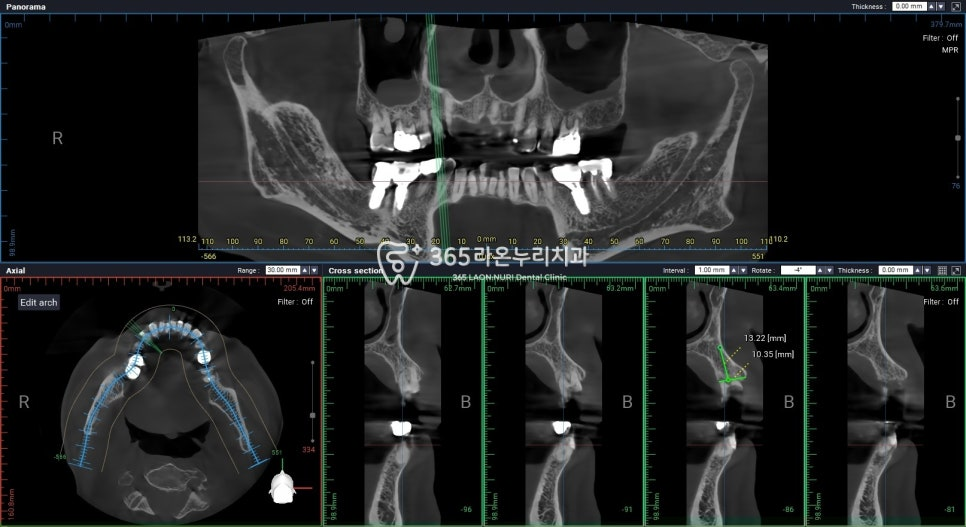

CT 촬영과 3D 자료를

이용하여 모의 식립을 할 수 있는데요.

2025.1.2

수술 가이드를 제작하여

인공 픽스처를 즉시 식립하는

방법이 있는데요.

정밀 진단으로 미리 골 조직이나

신경 위치 등을 파악할 수 있어

정교하고 안전한 임플란트 수술 을

받을 수 있단 장점을 가지고 있습니다.